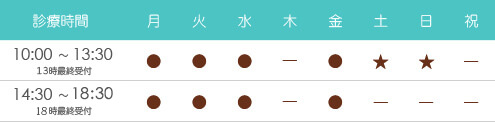

最大で20倍程度治療する部位を拡大して診ることができます。

このことにより、今までの肉眼による治療で見ることができなかった

箇所が見えることにより治療精度を格段にあげることができます。

①根管治療(根っこの治療)

今までは手による感覚が主としてきた治療において、見えなかったことが見えることにより

残せなかった歯が残すことができたり

歯がわれていることが早いうちにわかり無駄な治療期間がかからなかったり

完全に取り除くことができなかった汚れをとることができる

治療期間の短縮と治療後の歯の寿命を長くすることが可能になります。

②むし歯治療

では、肉眼では発見することが難しかったむし歯を早期に発見できることにより、歯を削る量が少なくすることができ、また詰め物の精度をあげることにより歯の寿命を延ばすことが可能になります。

③補綴治療(かぶせものの治療)

においても精度をあげて作製することができるので

二次的にむし歯になるリスクを下げることが可能になります。

下の写真はむし歯治療をマイクロスコープで行った症例です。

黄色の矢印の先の茶色くなっている箇所が、小さなむし歯です。

これをマイクロスコープにて治療することにより詰め物と歯の境目がわからないレベルまで詰めれていることが確認していただけると思います。